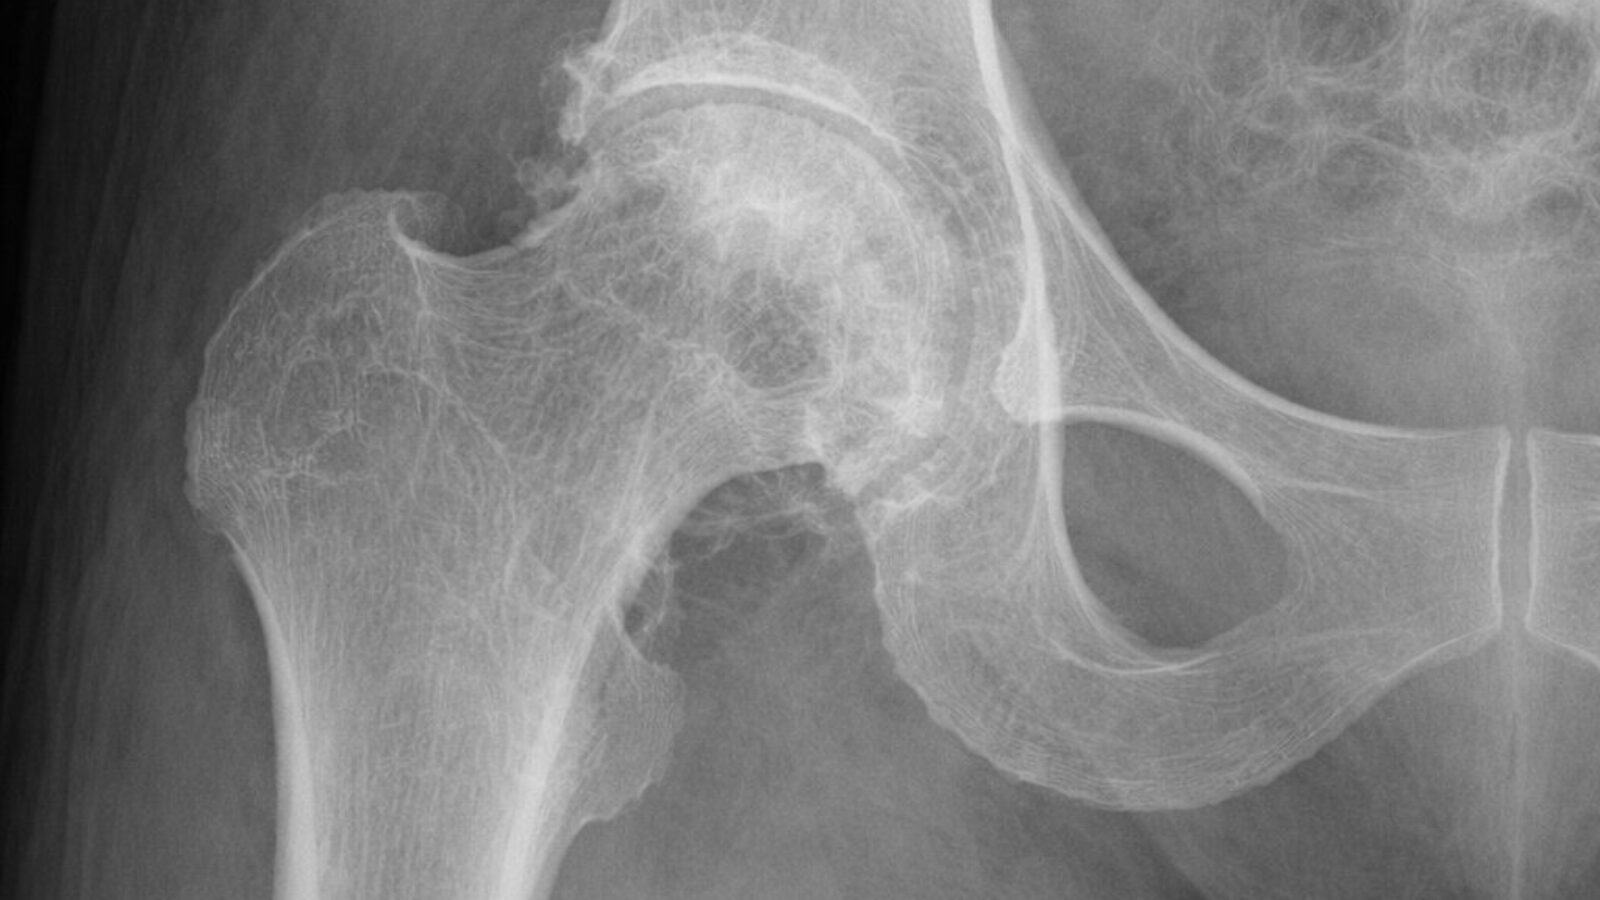

Would you know an AI X-ray if you saw one?

More AI news! Before we get into it: there's no evidence that deepfake X-rays are causing any disruption in health systems. Still, "Anyone could be confronted at some point with a fake X-ray and should be able to differentiate real and fake," researcher Mickael Tordjman told STAT's Katie Palmer.

In a new study including 17 radiologists, Tordjman found that fewer than half noticed that something was off when asked to diagnose patients based on fake imaging. Even when they were warned to look out for deepfakes, the doctors only differentiated them accurately 75% of the time.